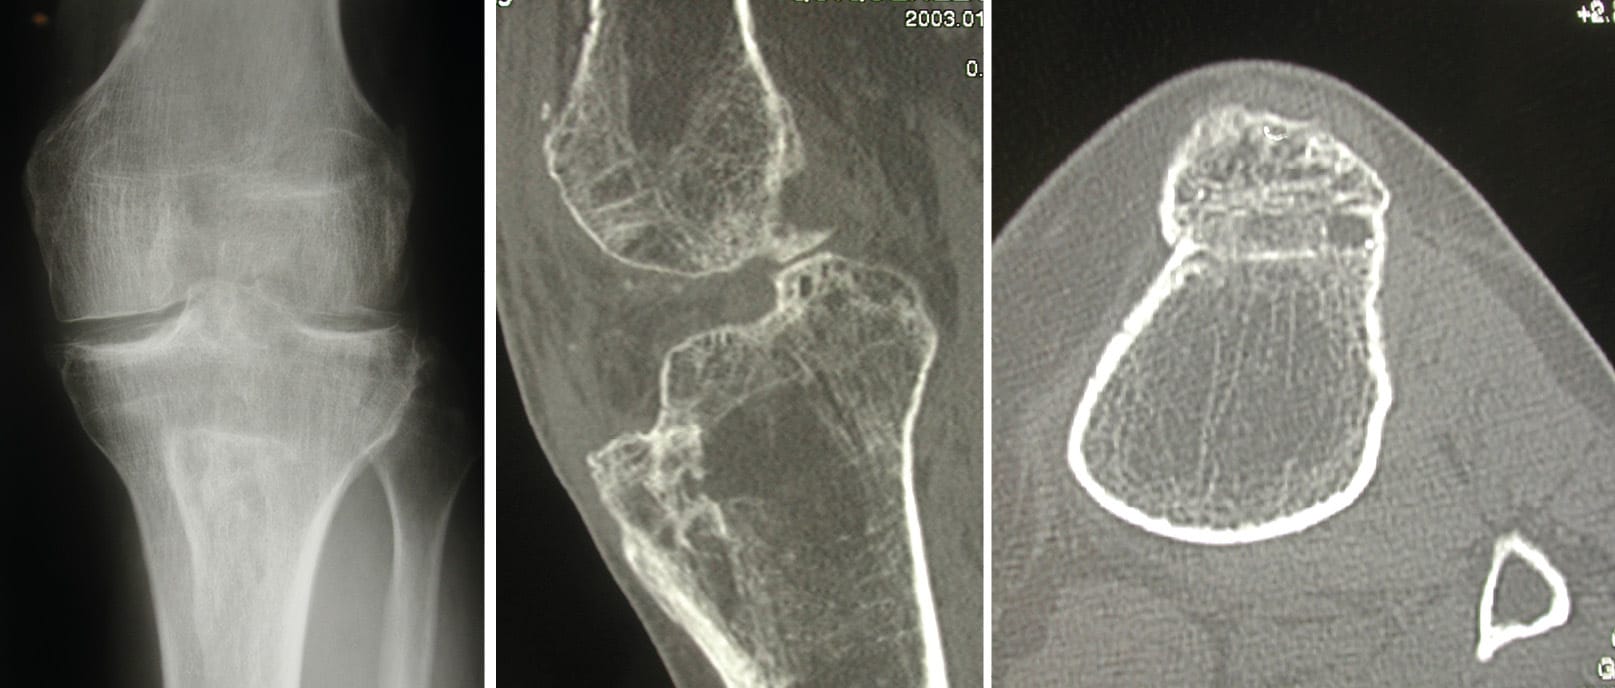

First, the fundamental factor: Trochlear dysplasia [1], Hallab NJ, Jacobs JJ. Biologic effects of implant debris. Bull NYU Hosp Jt Dis. 2009;67(2):182-8.. A brief historical note: during the preparation for the 1987 LYSKS DAYS, the article by Malghem and Maldague, two Belgian radiologists, was published. Coincidence or not, the Lyon studies and the Belgian publication reached the same conclusion. The analysis of the lateral X-ray view provided previously overlooked information regarding the morphology of the trochlea and its possible dysplasia. Previously, only the axial view was considered.

A good lateral X-ray of the knee meets specific criteria (Figure 14). It is performed at 30° of flexion with the two posterior condyles superimposed. To optimise this superimposition, a brief fluoroscopy may be performed. The patient can be lying on the X-ray table or in single-leg stance.

The axial view of both patellae must be performed with both knees flexed at 30° and no more, as is too often the case. Both knees are on the same cassette. We no longer request a series of views with the knee flexed at 60° and 90° or in external rotation.

On this diagram of the lateral knee (Figure 15), one can recognise the trochlear groove line A, but also the two condyles, lateral B and medial C. This trochlear groove line A remains distant from the lines of the two condyles B and C. In fact, on the axial view, these three lines are found with the medial and lateral facets of the trochlea, as well as the trochlear groove line.

The axial view (Figure 16) is conventionally performed at 30° of flexion. It does not account for the proximal part of the trochlea. The lateral X-ray allows for the analysis of the trochlea from its most proximal part down to the notch.

This is the true value of the lateral view: The analysis of the proximal portion, the upper part of the trochlea.

On this lateral radiograph (Figure 16), one can recognise the trochlear groove line but also the two condyles, lateral and medial. This trochlear groove line remains distant from the lines of the two condyles. In fact, these three lines are found on the axial view, with the medial and lateral facets of the trochlea as well as the trochlear groove line. The trochlear groove line always remains distant from the line of the two condyles, even in its proximal part.

Here is a very clear crossing sign (Figure 17) on the lateral radiograph. From this point upwards, the trochlea is flat or even convex. As the crossing occurs quite low on the trochlea, it is very dysplastic, and this can be diagnosed on the axial view at 30° of flexion.

The spur or prominence (Figure 18) is the second essential sign of trochlear dysplasia after the crossing sign. To demonstrate it, a tangent to the anterior cortex is drawn. This line can pass anterior to, at the level of, or posterior to the most anterior point of the trochlear groove line. One can therefore have a negative, zero, or even positive prominence value when this tangent passes posterior to the most anterior point of the trochlear groove.

The mean prominence value was -0.8 mm in a control group, while the mean was 3.2 mm in the group of patients who had experienced one or more patellar dislocations. More importantly, a threshold value of 3 mm could be defined (Figure 19).

Trochlear depth is less well known (Figure 21). It is the third factor that we must analyse on a lateral radiograph. It gives us valuable information about the congruence of the trochlea at 15° of flexion. It represents the distance between the trochlear groove line and the lateral facet. It allows us to know if the trochlea deepens distally. Comparing a group of patients who had experienced one or more patellar dislocations and a control group, a threshold value of 4mm was determined.

The depth, measured at 15°, is not deep enough, not congruent enough, if the depth is less than 4mm. This factor, less essential diagnostically, is crucial prognostically and guides our therapeutic choices. If the trochlea is well-grooved at 15° of flexion, then bringing the patella to face this congruent trochlea, for example by distalisation of the ATT, often ensures good patellar stability.

This analytical study of trochlear dysplasia criteria led to a synthetic classification into three types (Figure 22), which was presented in 1987. From type 1 to the more severe type 3, the crossing occurs from the proximal to the distal part of the trochlea. Dysplasia can thus be classified from the first consultation with a simple, correctly performed lateral radiograph.